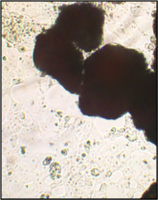

Образец исследуемого материала - кусочек недеминерализованной спонгиозы серии «Лиопласт»® объемом 125 куб. мм (рис. 31) помещали на равномерный монослой фибробластов плотностью 332 клетки/ммІ.

Этот материал имеет нейтральную реакцию (рН=7,2). Так как рН ростовой среды также 7,2-7,3, внесение образца не изменяет реакцию.

Рис. 31. Недеминерализованная спонгиоза серии «Лиопласт»®.

Через сутки монослой как в контроле, так и в опыте был целостным и равномерным, фибробласты сохраняли обычную форму и размеры.

Клеточная и ядерная оболочки четко контурировали.

Цитоплазма представлялась гомогенной.

Большинство клеток имели одно центрально расположенное ядро правильной округлой формы с 1 или 2 ядрышками.

Количество поврежденных клеток - 3%.

Плотность монослоя в опыте составляла 774 клетки/ммІ, в контроле 643 клетки/ммІ.

Таким образом, время удвоения культуры в опыте – 22 часа, в контроле –24 часа (табл. 6).